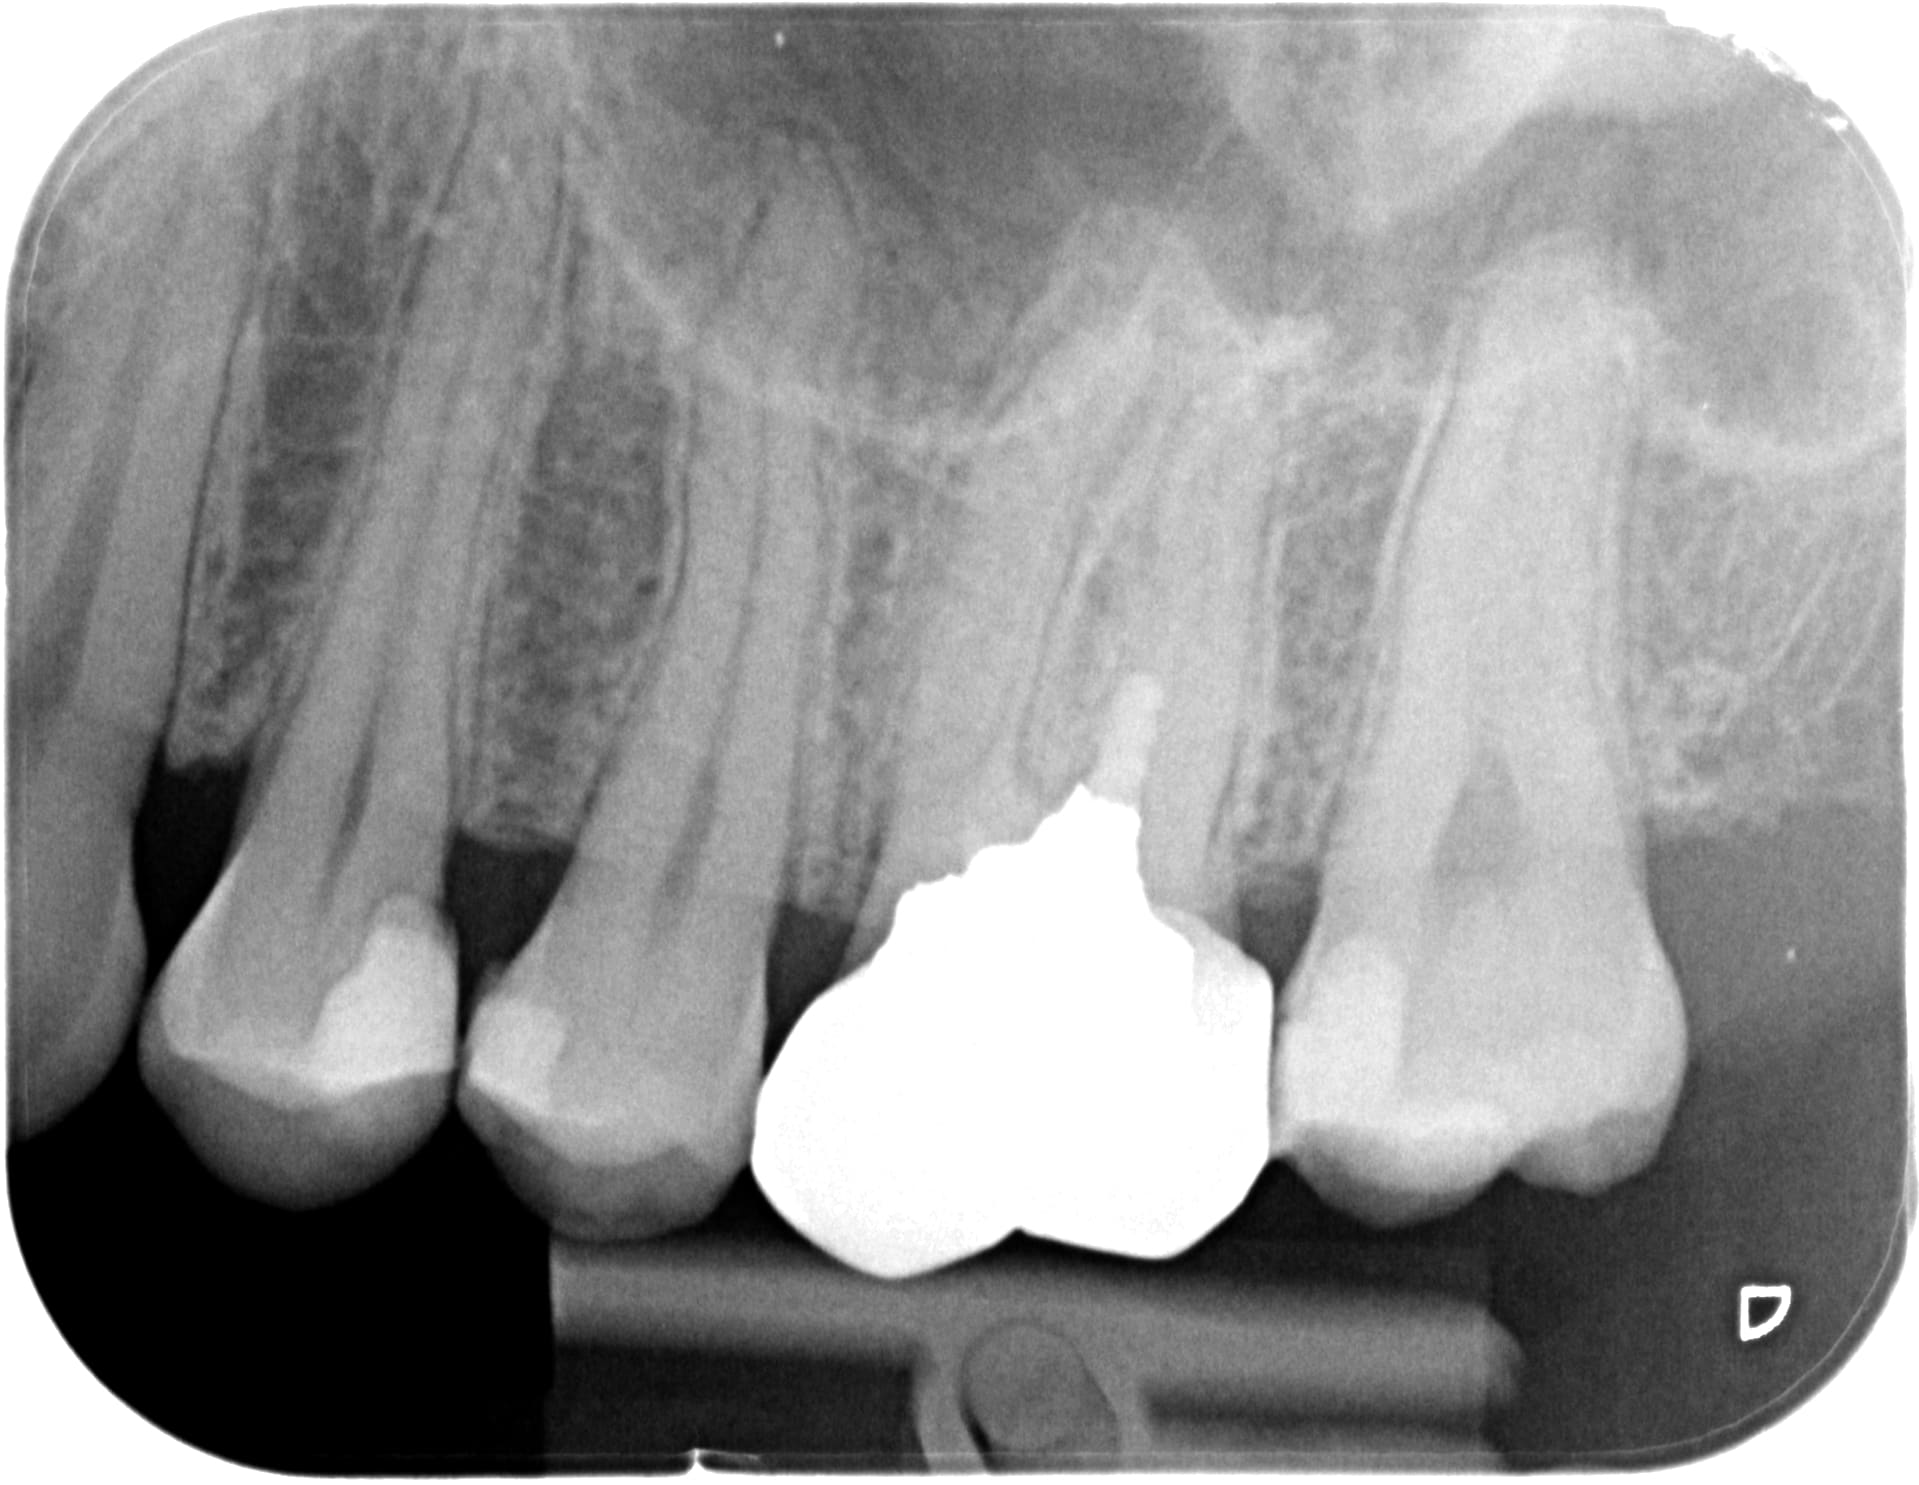

Mode humour ON -Ah j'en ai trouvé encore moins doué que moi en endo...-

ça me rappelle le début de mon exercice il y a bientôt 30 ans ou ce genre de "traitement" était courant...

et m'a permis de démarrer très rapidement mon activité..Tout à fait d'accord sur les analyses précédentes: en milieu rural ce qui compte c'est qu'on soit présent ..la qualité passe après ( au moins dans un premier temps..ensuite, les patients ne sont pas plus stupides qu'ailleurs et parlent entre eux: beaucoup plus efficaces que toutes les pub et sites internet du monde !!!...)